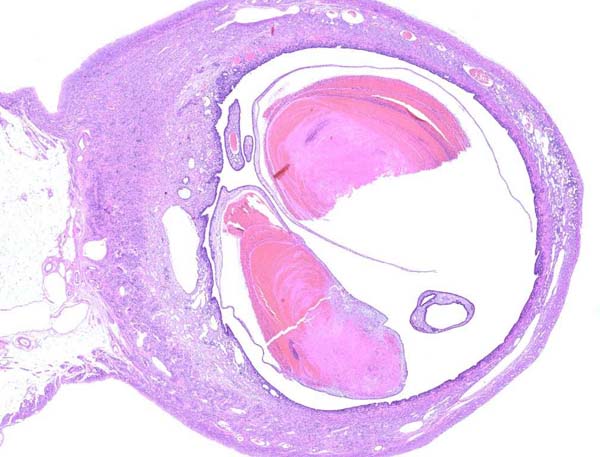

ウサギの子宮内膜過形成の手術(エキゾチック)

陰部からの出血を繰り返し、元気食欲がないとのことで来院されました。エコー検査にて子宮に腫瘤を認め、手術にて摘出しました。病理組織検査の結果は「顕著な血管拡張および血栓形成を伴う子宮内膜過形成」でした。「子宮においては血栓形成を伴った過形成性の病変が認められました。過形成による血流阻害が一因として考えられます。卵巣においては腫瘍性の変化は認めませんでした。」とのコメントでした。翌日元気に退院されました。「ウサギさんが10歳まで長生きしたらほぼ100%近く子宮の病気になる」という説があります。飼育下のウサギさんが長生きするためには早期の避妊手術が必要であると考えられます。